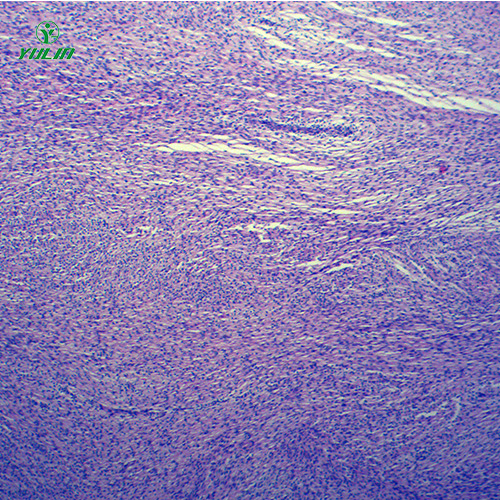

人体病理切片,人体肿瘤病理玻片,人体肿瘤病理玻片价格